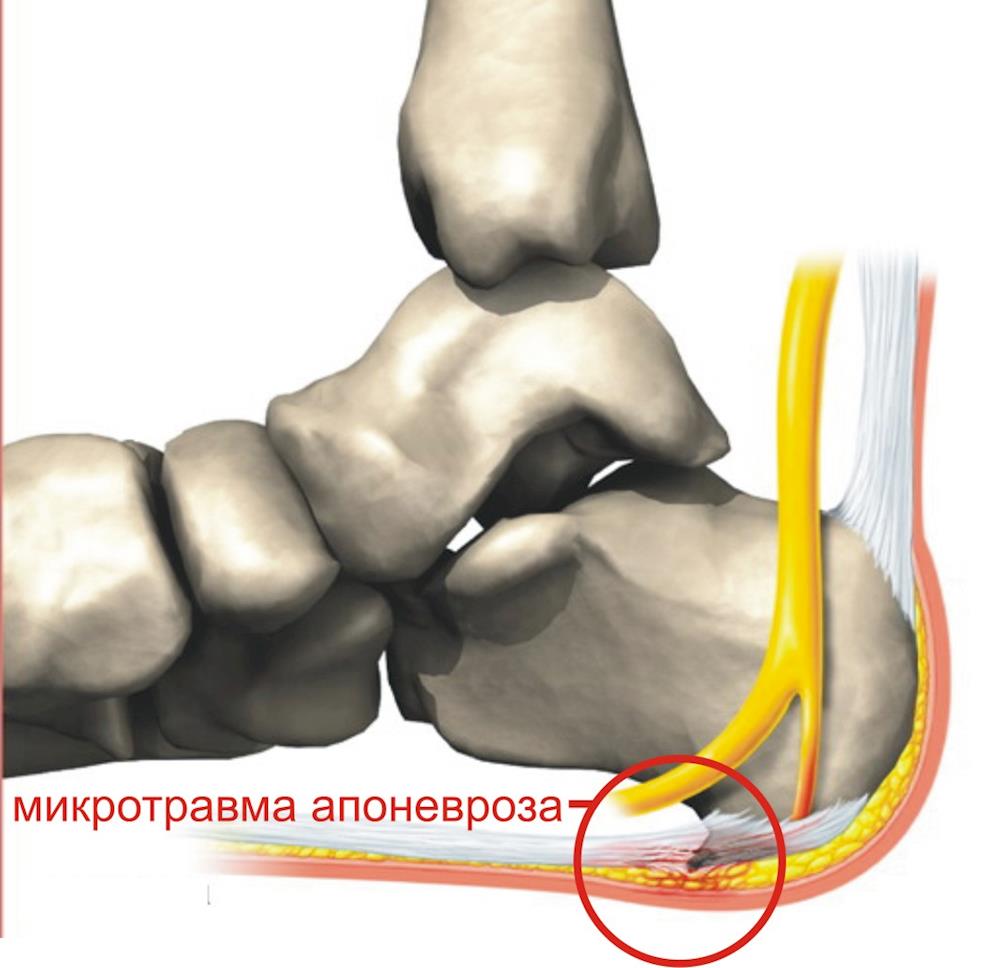

Стопа человека по своему строению напоминает арку, и поэтому ее небольшие по массе и толщине кости выдерживают огромную нагрузку. Аркообразность свода стопы поддерживается с подошвенной стороны мощнейшей связкой - подошвенным апоневрозом. Задний конец подошвенного апоневроза прикреплен к пяточной кости, а 6 расходящихся пучком передних – к пальцам стопы. Таким образом, он связывает передний и задний отделы стопы и удерживает стопу от распластывания.

Механизм повреждения.

Смещение центра тяжести тела вперед (сутулость, избыточный вес, слабость мышц голеней), особенно в сочетании с ходьбой, бегом или прыжками, приводит к многократным микроотрывам волокон апоневроза от пяточной кости, а заживление поврежденных волокон происходит путем превращения поврежденной части апоневроза в кость.

Как возникает боль?

Боль при опоре на стопу возникает в основном из-за появления новых надрывов апоневроза, а не из-за давления шпоры на ткани стопы.

Поэтому пяточная шпора не причина, а следствие заболевания.

Именно так и появляется видимая на рентгеновских снимках пяточная шпора.